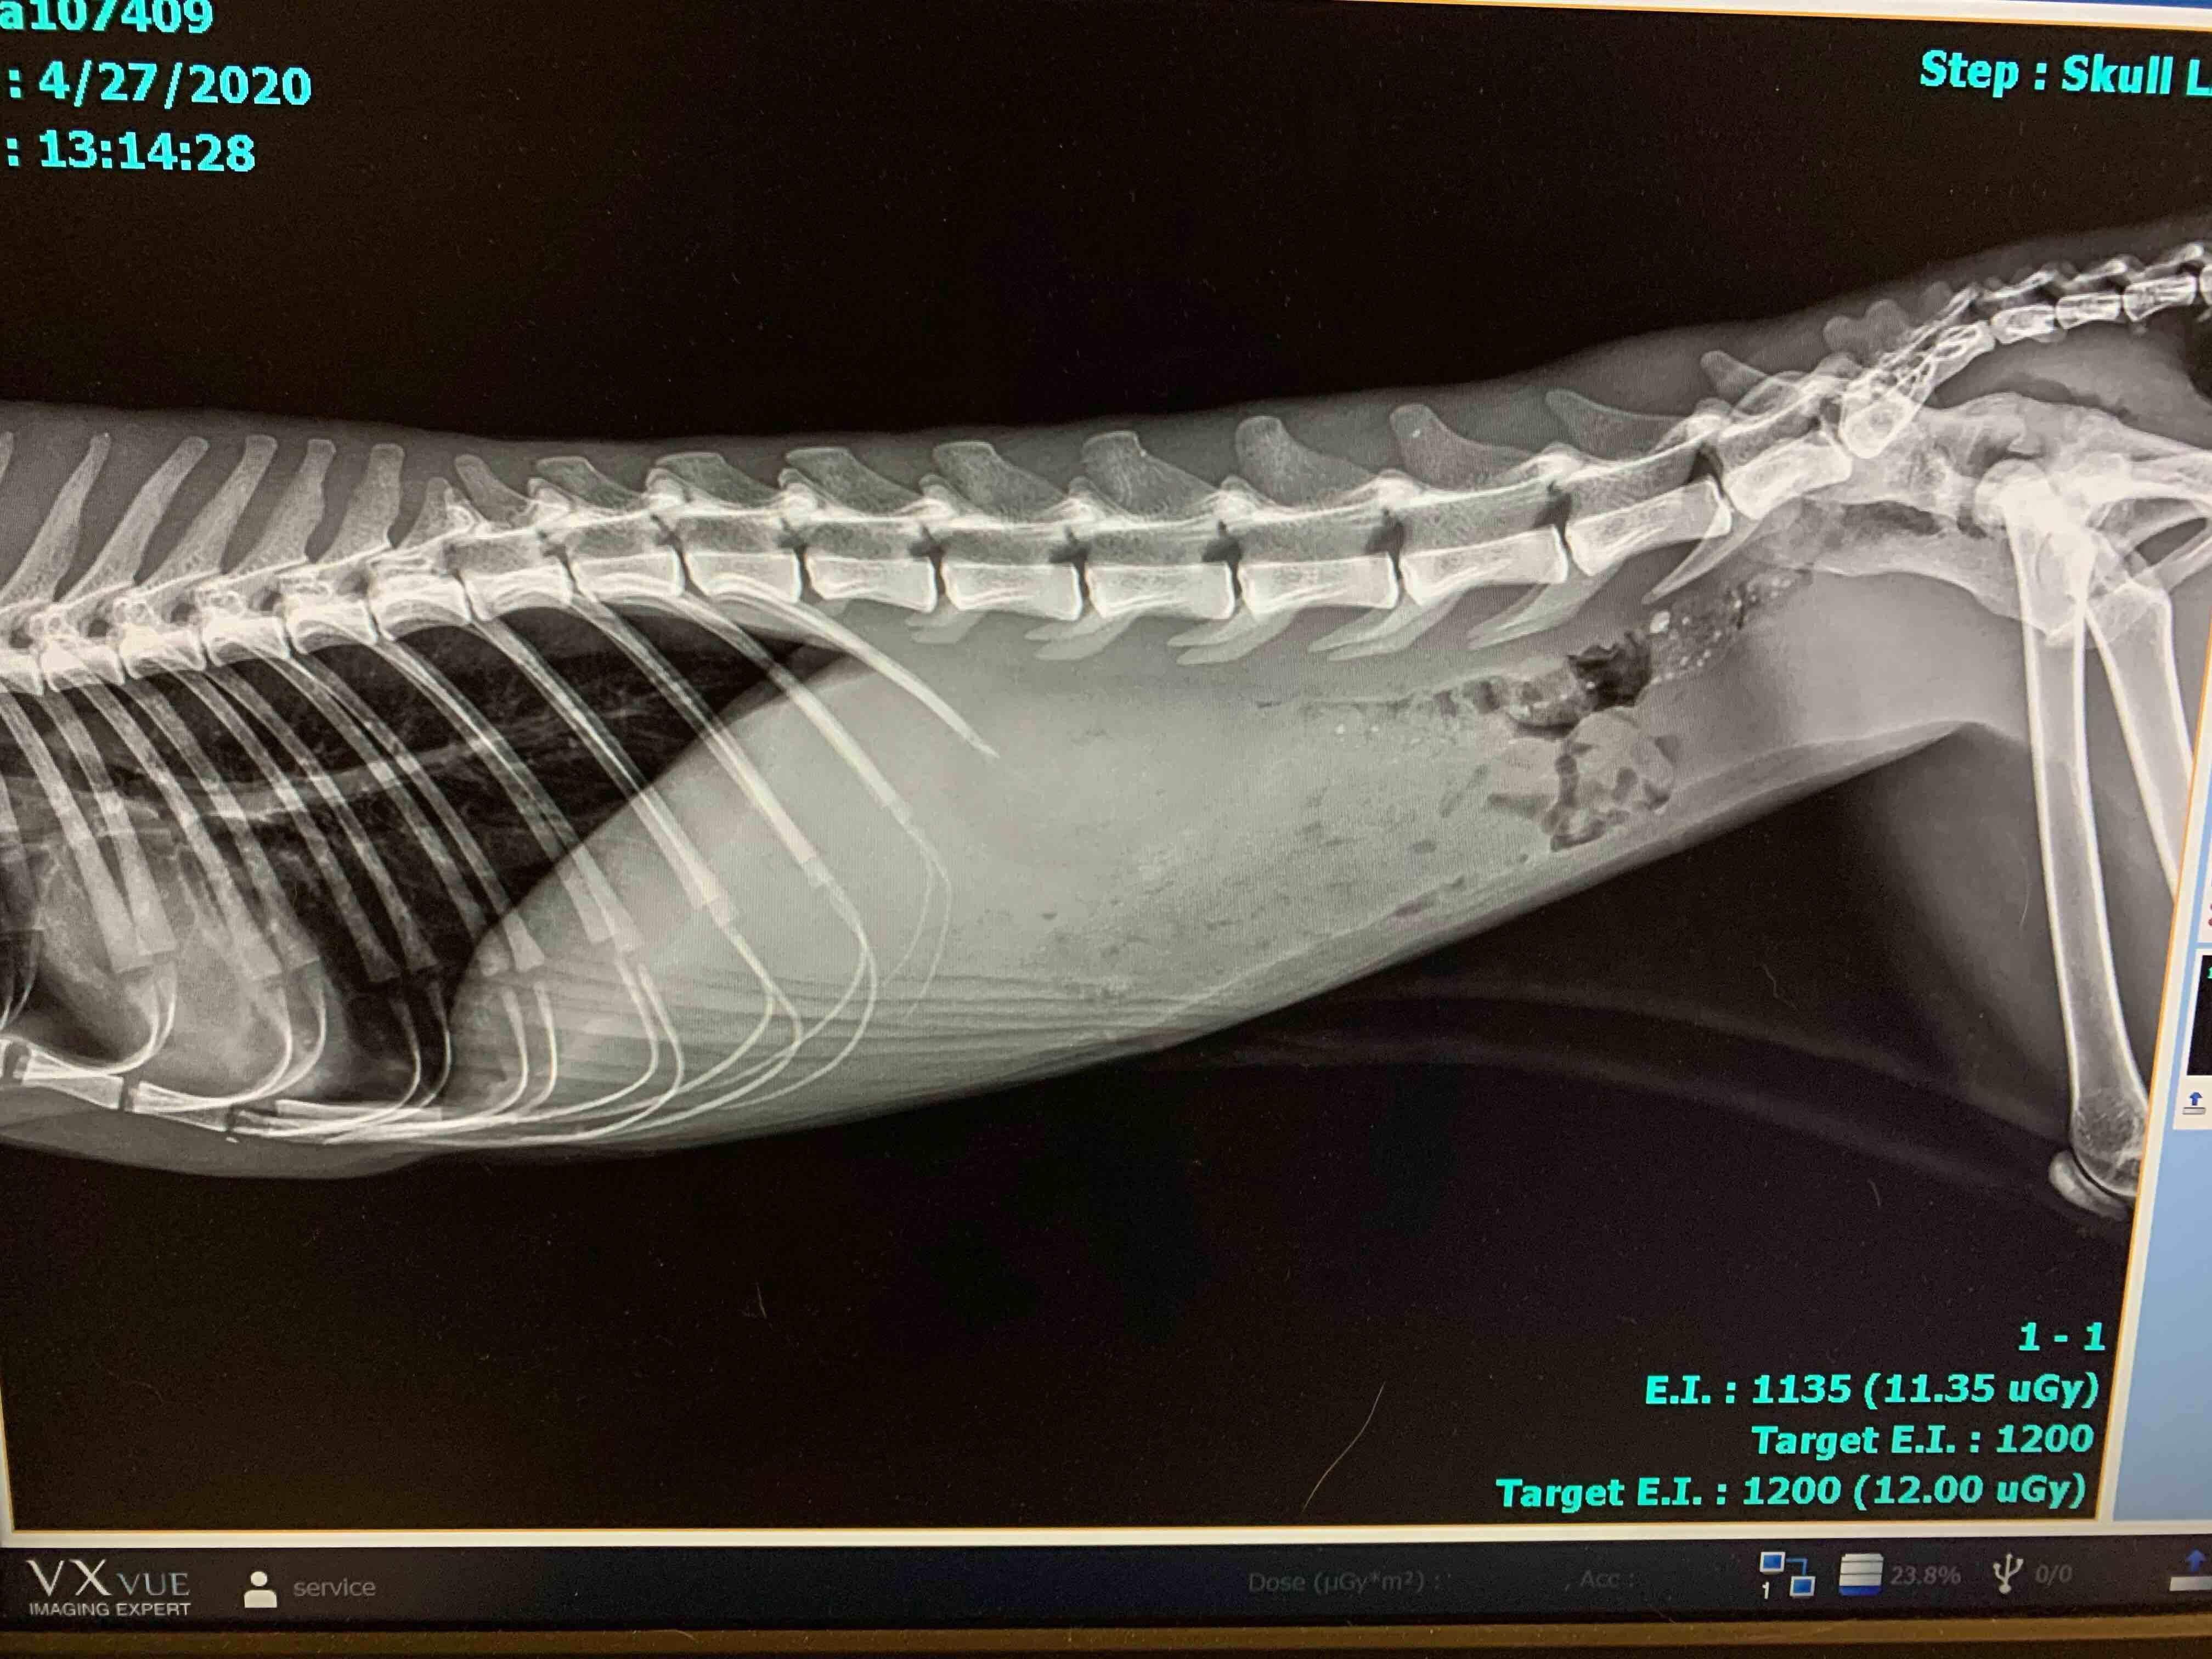

I need your advice I have a street cat who was healthy now he is very thin with thick phlegm. I took him to the vet they said he has viral and bacterial infection along with fluid accumulation in the abdomen. Is it FIP? Is he in pain?

That x-ray shows a lot of free fluid in the abdomen. It very likely could be FIP and if so, yes he is probably in some pain. A fluid sample from that abdominal fluid would need to be tested to check for FIP. He has some other abnormalities on the blood testing (like a high protein) that also points to FIP.